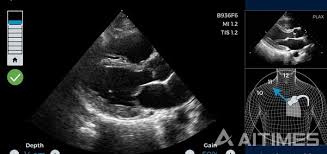

심장 초음파로 알 수 있는 병 ② 심장 판막 질환

심장에는 혈액의 흐름을 조절하는 판막이 존재합니다. 심장 초음파는 판막이 제대로 열리고 닫히는지, 역류가 있는지를 정확하게 보여줍니다.

- 승모판막 협착·폐쇄부전

- 대동맥판막 협착·역류

이처럼 판막 이상은 대표적인 심장 초음파로 알 수 있는 병에 해당하며, 심잡음이 들릴 때 필수적으로 시행됩니다.